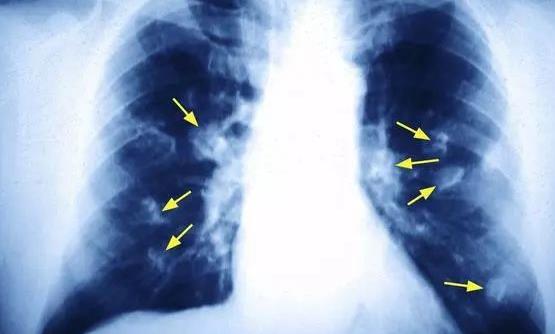

我国国家癌症中心的最新报告显示,肺癌是女性第二高发的癌症,仅次于乳腺癌。40-50岁女性中肺癌患者人数已经接近男性,达到了1:1的比例。但是国内女性的吸烟率很低,为何发生肺癌的概率却如此“不协调”地高呢?下面跟随360常识网了解一下吧!

对肺癌患者长达5年的追踪病因调查发现,70%的男性肺癌患者死于吸烟病因,只有18%的女性患者因吸烟或长期被动吸烟致肺癌。

当然是做饭!调查发现,在不吸烟的女性肺癌患者中,超过60%的女性不仅在家做饭,还在厨房中长期吸入油烟。

在非吸烟女性肺癌危险因素中,超过60%的女性长期接触厨房油烟;有32%的女性烧菜喜欢用高温油煎炸食物,同时厨房门窗关闭,厨房小环境油烟污染严重;25%的女性家中厨房连着卧室,冬天又很少开窗,高温油烟久久不散,甚至睡觉时也在吸油烟!

调查表明,这种病因在中老年女性肺癌患者中特别突出,危险因素达到了正常人的2-3倍。

这是由于厨房做饭时高温油烟产生有毒烟雾,使局部环境恶化,有毒烟雾长期刺激眼和咽喉,损伤呼吸系统细胞组织,如果没有足够的防护措施,就很容易使肺癌发生。